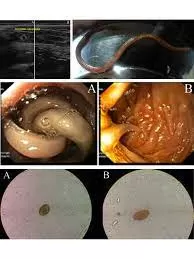

- دودة الإسكارس (Ascaris lumbricoides) هي واحدة من أشهر الديدان المعوية التي تصيب الإنسان، خاصة الأطفال. تنتمي إلى الديدان الأسطوانية، وتعيش داخل الأمعاء الدقيقة حيث تتغذى على المواد الغذائية التي يتناولها المصاب.

- دودة الإسكارس هي نوع من الديدان الطفيلية التي تصيب الجهاز الهضمي للإنسان، وخاصة الأمعاء الدقيقة. يمكن أن تنمو حتى 35 سم في الطول وتسبب مشكلات صحية إذا لم يتم علاجها.

دودة الإسكارس تبدو في البراز كدودة طويلة، بيضاء أو صفراء، وقد تكون حية وتتحرك أو ميتة وثابتة. يمكن أن يصل طولها إلى 35 سم، وتكون عادة دائرية الشكل مثل المعكرونة الرفيعة.

تبدأ دُودة الأسكارس دورة حياتها داخل الأمعاء البشرية ثم تنطلق إلى الخارج عبر البراز لتنتقل إلى شخص آخر وتستقر في أمعاءه وهكذا حيث أن مراحل حياتها تبدأ بالبيضة ومن ثم تتحول إلى يرقة ومنها إلى عذراء وأخيرًا تنضج وتتحول إلى دودة أسطوانية الشكل تخترق أمعاء الإنسان.